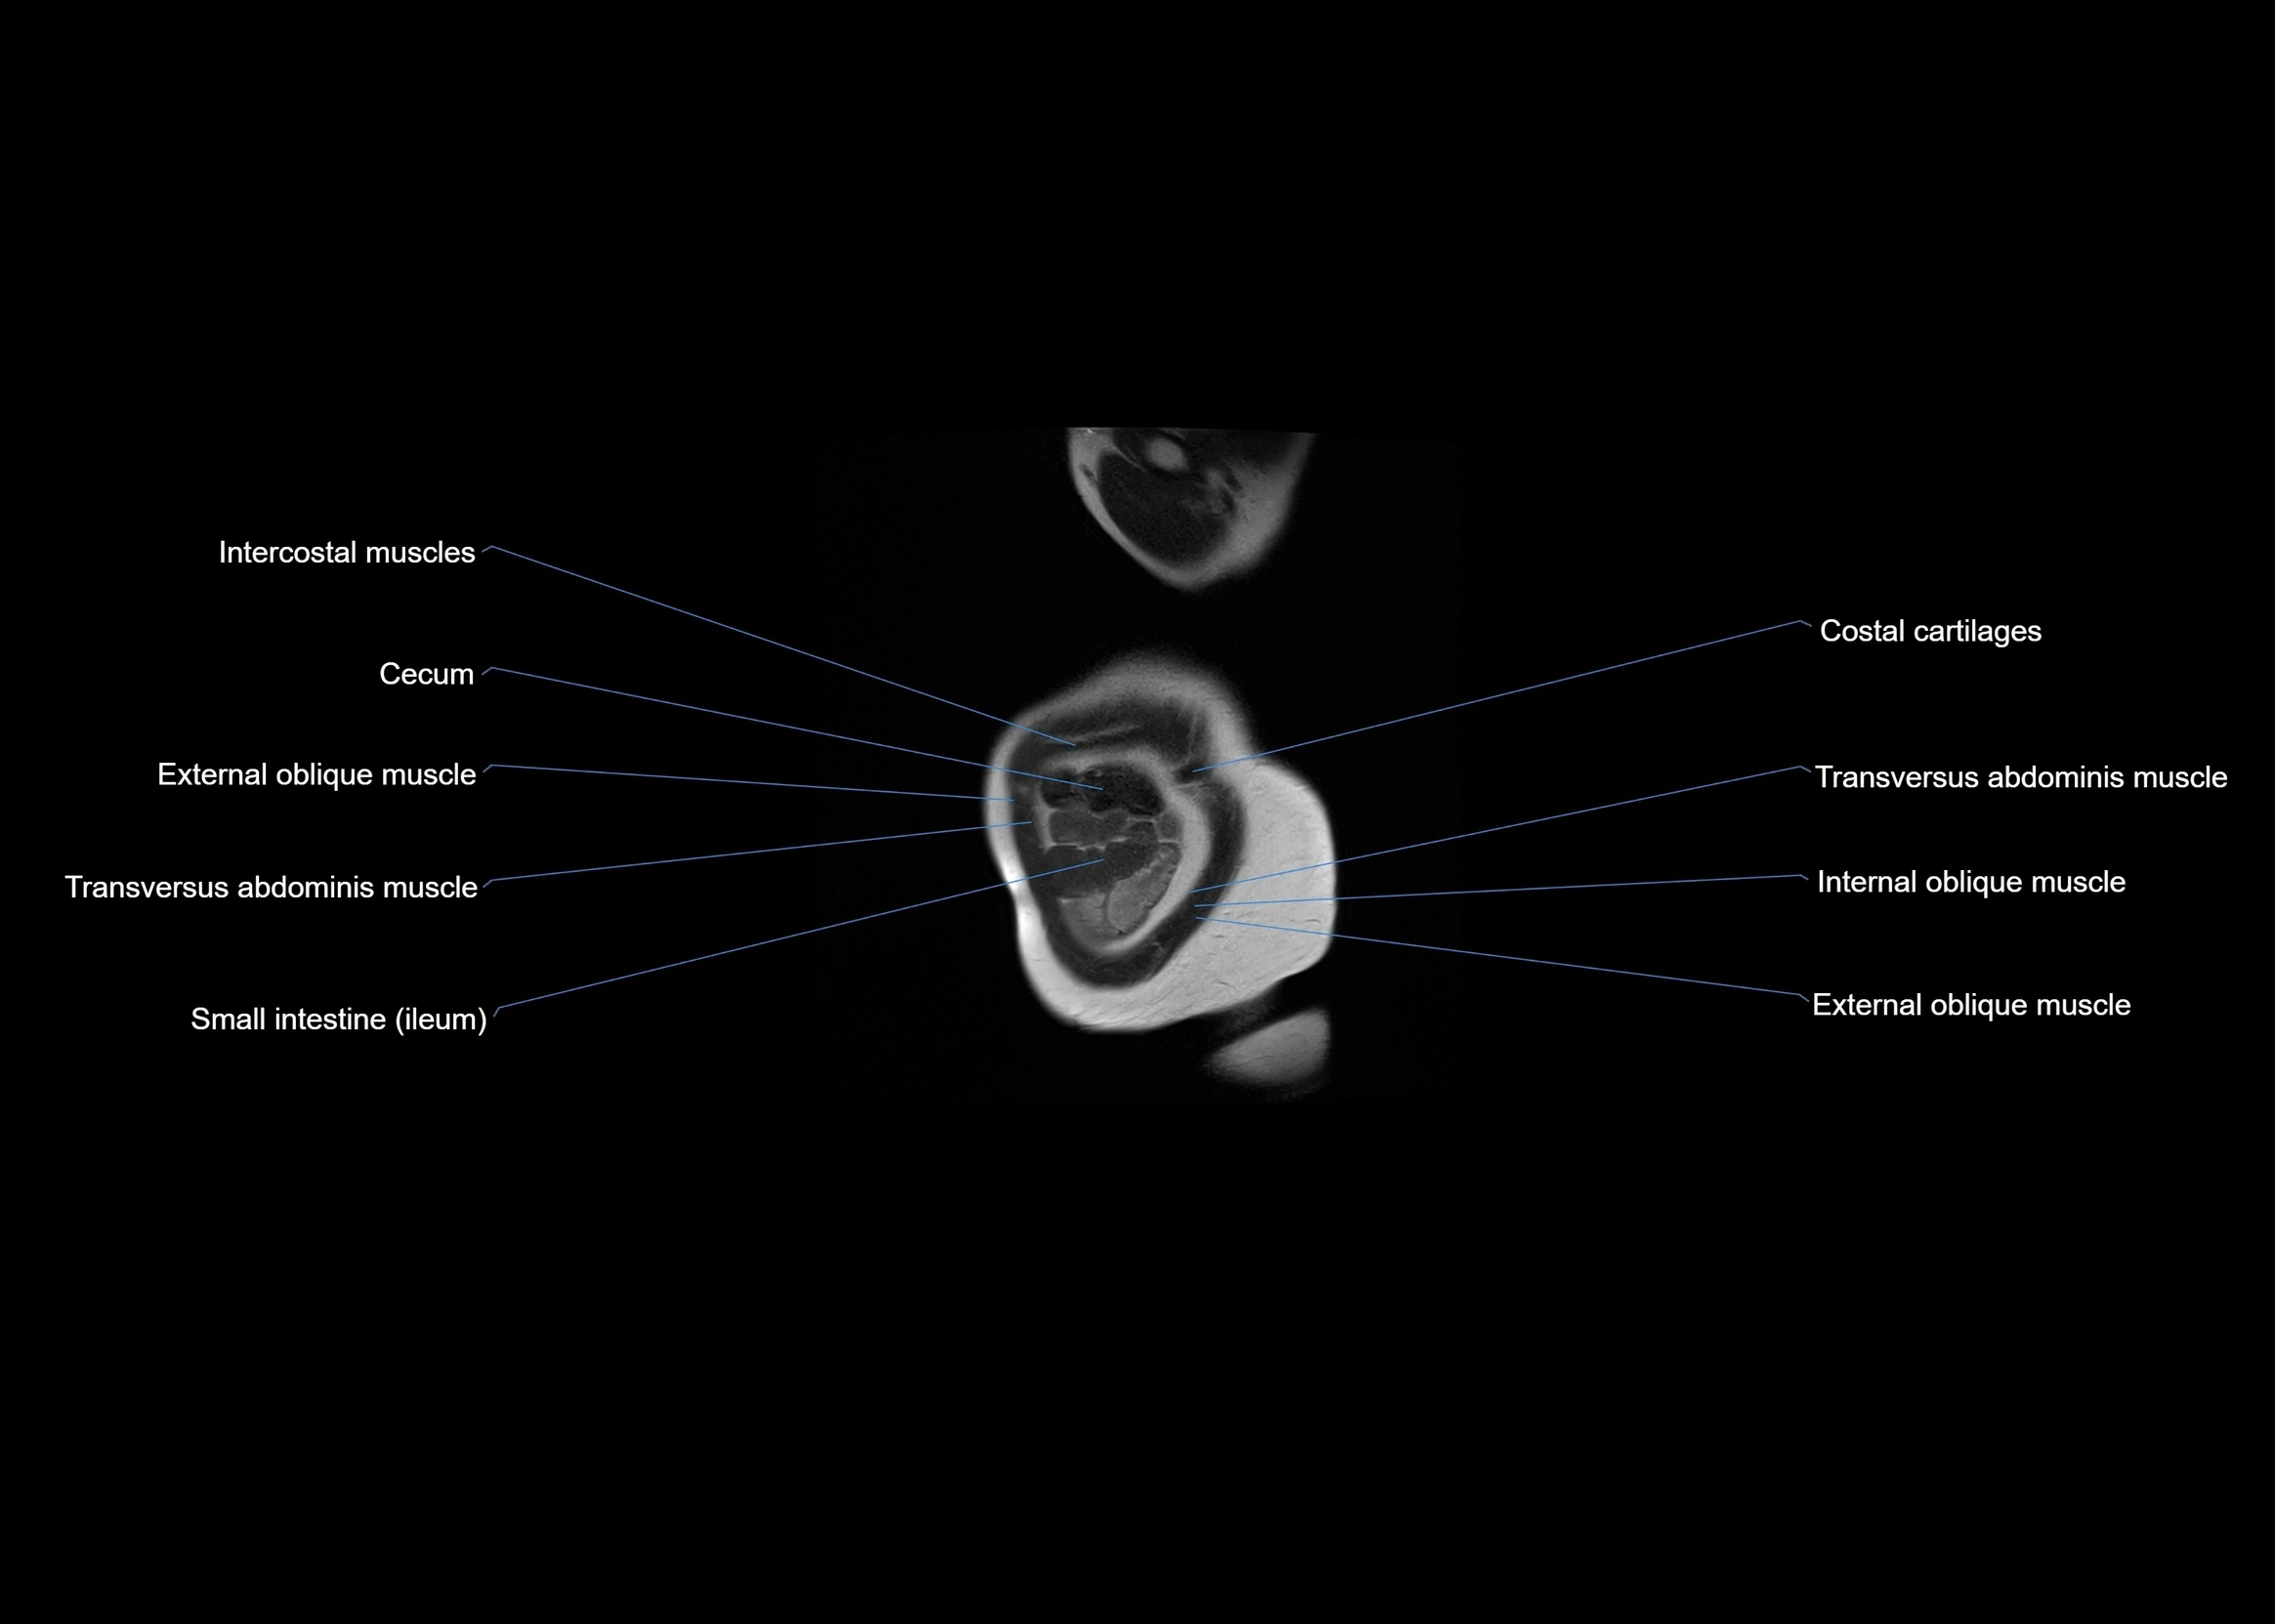

MRI images